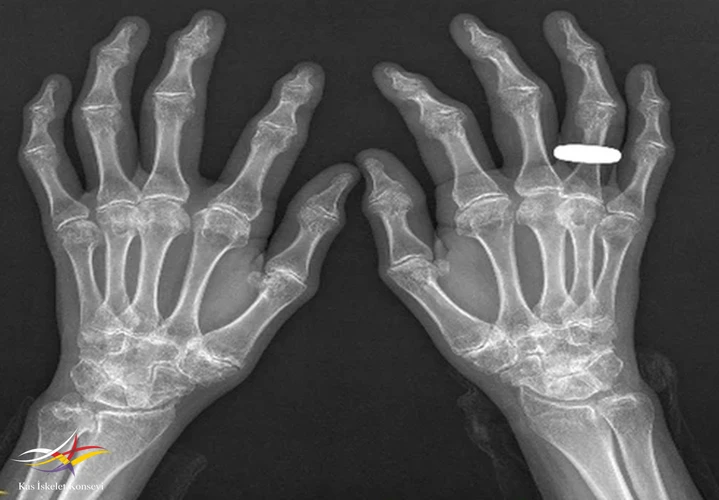

Resim 3.

Muayene: Fizik muayenede omuz, el bilek,dirsek, kalça, ayak bilek rom kısıtlı. El PIF'lerde şişlik, büyümüş kemiksi eklem görünümü? Boy kısa, kifotik görünüm mevcut? Artrit yok, ateş, kilo kaybı,oral aft genital ülser, ağız göz kuruluğu, Raynauld fenomeni yok.

İncelemeler: Biokimyasal tetkikler normal, RF VE ANTİ CCP (-).

2. Epifizyal değişiklikler: Uzun kemiklerin epifizlerinde irregular yapı, morfolojisi bozulmuş epifizler.

Bu hastalar erken yaşta JRA, ileri yaşta SERO–RA tanısı alıp gereksiz immunsupresif tedavi alabilirler.